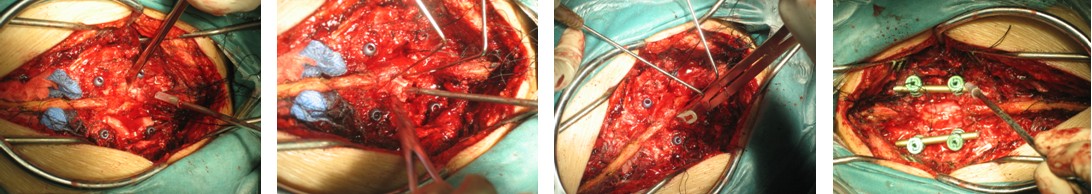

4. 典型病例:病例1,患者男性,40岁,司机。主因胸腰背部疼痛3年,肛周麻木、性功能减退并伴双足下垂2年,症状加重且二便肥力、无法工作1年入院。入院查体:一般情况良好,体胖、体重105kg。步态不稳,步行缓慢。胸腰段脊柱背部轻压痛,无放射。双侧股四头肌力IV级,双侧胫前肌力I级,双侧足下垂。鞍区感觉减退,无病理征。双侧跟、膝腱反射消失。血化验检查正常。X线平片显示T12~L1椎间隙明显变窄。CT显示T12~L1椎间盘突出并椎体后缘离断。MRI显示T12~L1椎间盘呈中央型突出,椎管狭窄,脊髓明显受压变形。入院诊断:T12~L1椎间盘突出症伴椎体后缘离断,马尾神经损害。术前检查完成后,在气管插管全麻下行上述经极外侧入路T12~L1椎间盘切除手术治疗,整个手术过程顺利,无术中及术后并发症发生,术后1周顺利出院。出院时,其双侧股四头肌、胫前肌肌力已分别恢复至V级和III级;鞍区感觉减退亦有明显好转。术后显示T12~L1突出之椎间盘及离断之椎体后缘已被完全切除,椎间融合器及椎弓根螺钉位置佳,脊柱局部生理曲度良好(图2a~2l)。病例2,女性患者,59岁。主因间歇性跛行,双下肢无力3年入院。入院诊断:T11椎体后上缘骨软骨瘤。以与病例1相同的术式行椎体骨软骨瘤的彻底切除(图3a~3l),无手术并发症发生,术后患者下肢症状明显改善。

图2e~2h. 典型病例1手术中情况: 关节突关节切除, 椎间盘切除, 椎间融合器植入及椎弓根固定

图3e~3h.典型病历2术中椎管后壁切除及极外侧显露情况